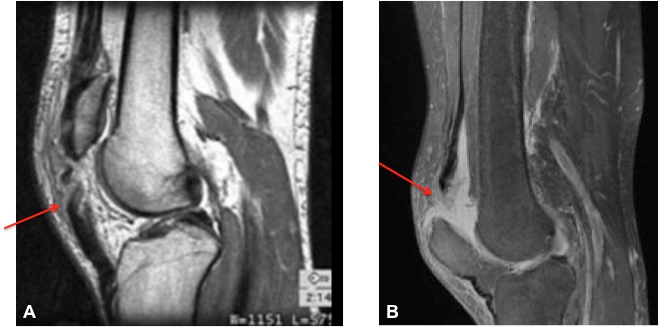

Ruptures De L Appareil Extenseur Du Genou Revue Medicale Suisse